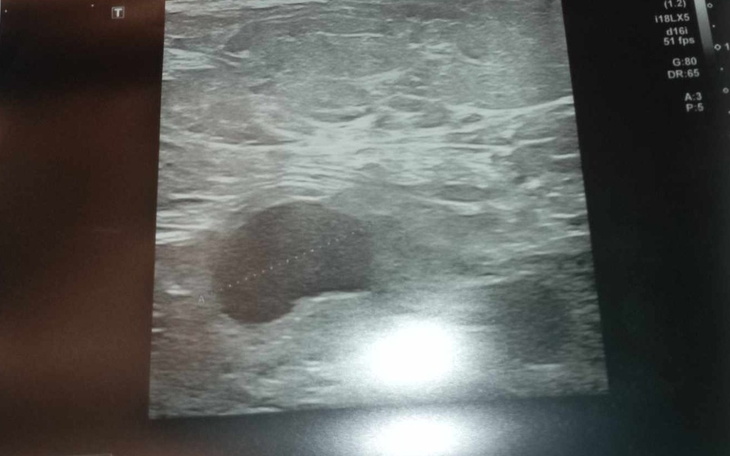

20 lutego mama usłyszała diagnozę że ma nowotwór złośliwy o piersi prawej z przerzutami do prawej jamy pachowej .Był to dla nas szok .22 lutego mój ojciec uciekł do kochanki , mam nadzieję że karma do nich wróci bo ta pani wiedziała że mama choruje na raka mimo to zrobili nam największe świństwo jakie jest możliwe .zostawiając załamana mamę i mnie . Myślałam że już nic nas nie zaskoczy ,ale 6 marca odbyło się konsylium lekarskie na którym mama dowiedziała się że nowotwór przekształcił się w zapalny i są nowe przerzuty do prawej okolicy nadobojczykowej .

ZDJĘCIA 👇👇👇👇